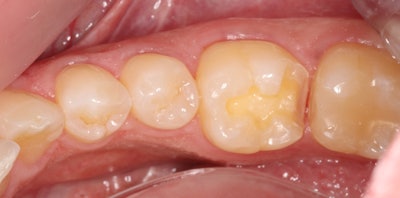

At this point, the Panavia SA Cement Universal was injected directly onto the onlay and seated. There was no need to apply a separate primer to the intaglio. It was then tack cured for 3 seconds (Bluephase G4, Ivoclar Vivadent, after which the excess could be peeled off, making for an easy cleanup.

Unlike most resin cements, Panavia SA Cement Universal provides virtually equal bond strengths whether light cured or self-cured for 2 to 4 minutes. The strength of the self-cure bond is within 1 megapascal of that achieved with light curing.

By choosing to proceed with an indirect restoration made of a hybrid ceramic block and bonding with Panavia SA Cement Universal, this procedure offered many advantages for both the clinician and the patient. This approach provided a superior restoration in terms of the hardness and lack of voids or porosities due to the restorative material. It also conserved tooth structure. Further, since it was an indirect restoration, C-factor stresses were greatly reduced, which will provide a durable, well-sealed restoration.